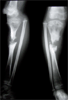

Infected non-union tibia in a 10year old child

Pre

Op

Xrays : Chroin osteomyelitis with bone gap proximally